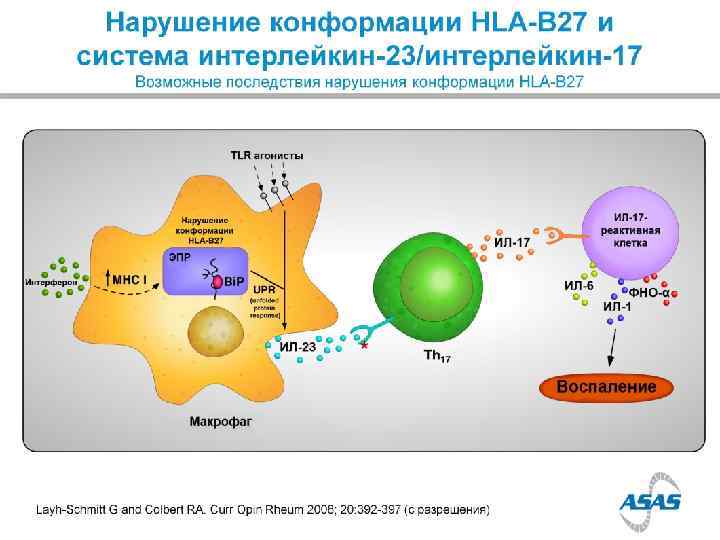

HLA B 27 1970 s HLA B 27 + in 90% of Caucasian AS pt Only 5% of HLA B 27+ persons will have AS HLA B 27 represents only about 25% of ‘genetic risk’ for AS